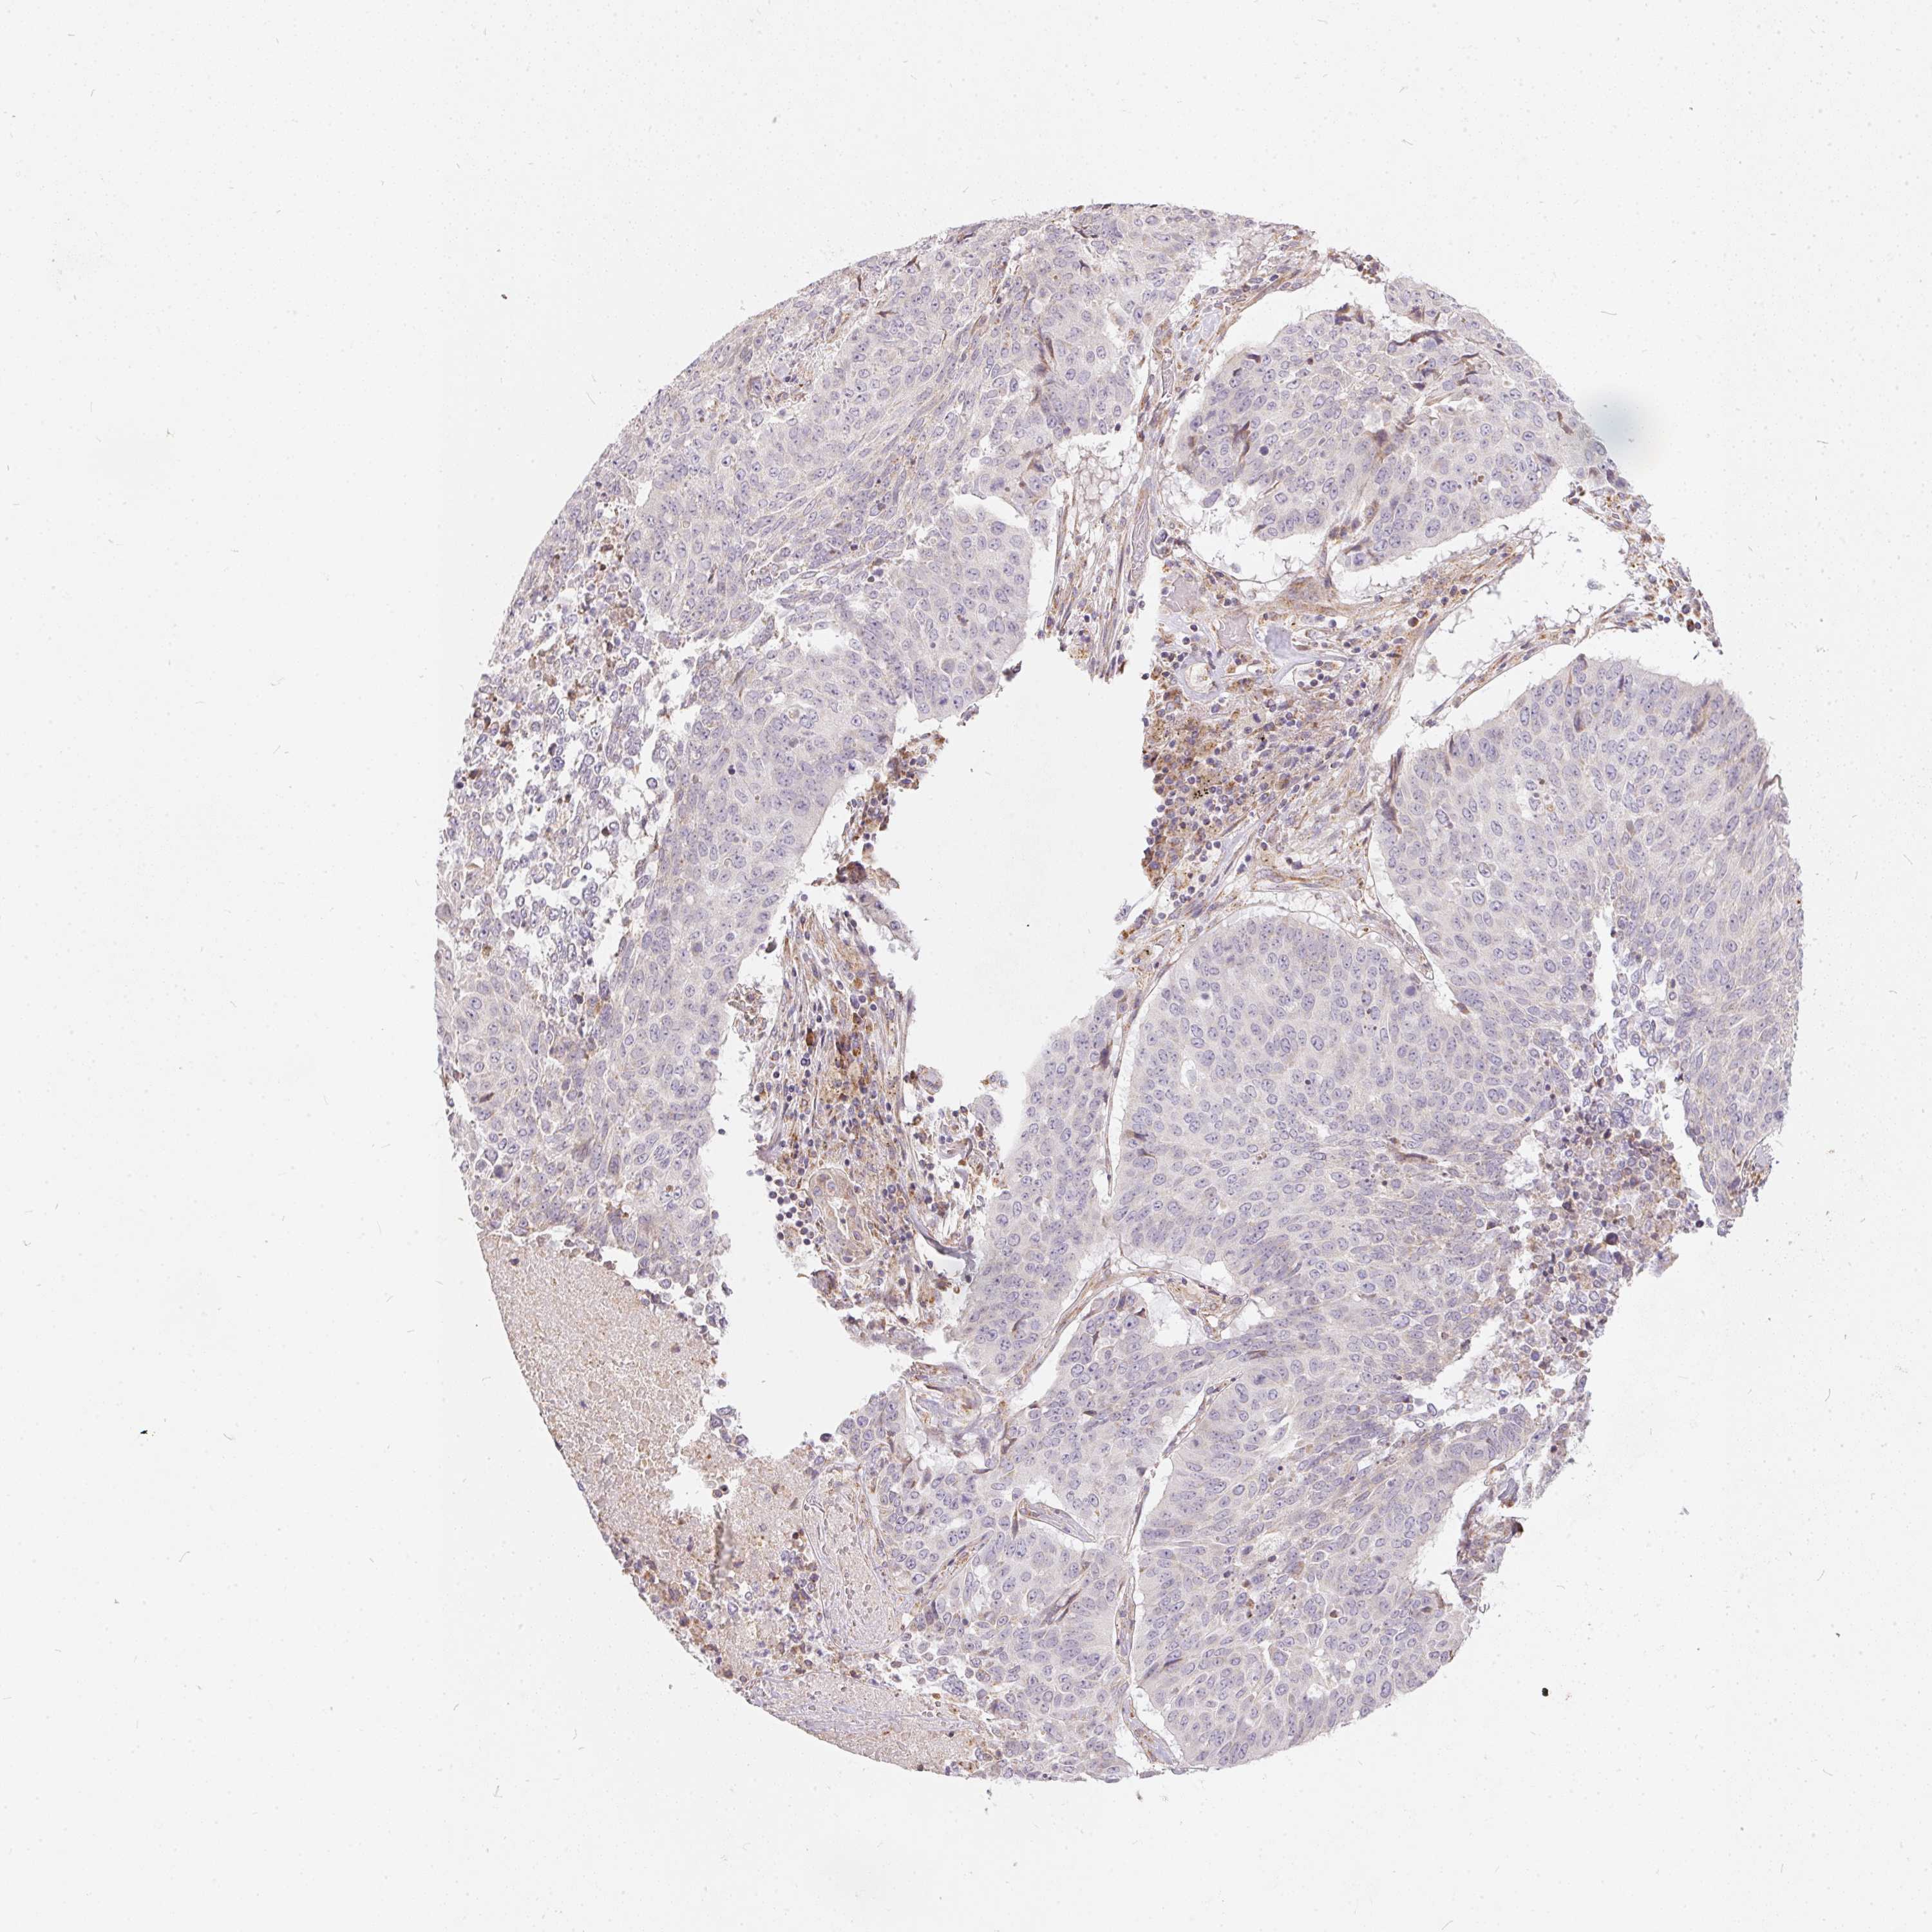

CANCER LUNG CANCER Show tissue menu

LUAD TCGA LUAD VALIDATION LUSC TCGA LUSC VALIDATION PROTEIN LUAD CPTAC PROTEIN LUSC CPTAC PROTEIN EXPRESSION

LUNG ADENOCARCINOMA (TCGA) - Interactive survival scatter ploti

The Survival Scatter plot shows the clinical status (i.e. dead or alive) for all individuals in the patient cohort, based on the same data that underlies the corresponding Kaplan-Meier plots. Patients that are alive at last time for follow-up are shown in blue and patients who have died during the study are shown in red.

The x-axis shows the expression levels (FPKM) of the investigated gene in the tumor tissue at the time of diagnosis. The y-axis shows the follow-up time after diagnosis (years). Both axes are complimented with kernel density curves demonstrating the data density over the axes. The top density plot shows the expression levels (FPKM) distribution among dead (red) and alive patients (blue). The right density plot shows the data density of the survived years of dead patients with high and low expression levels respectively, stratified using the cutoff indicated by the vertical dashed line through the Survival Scatter plot. This cutoff is automatically defined based on the FPKM cutoff that minimizes the p-score. The cutoff can be changed by dragging the vertical line or by entering a cutoff value in the square labeled "Current cut-off".

Under the Survival Scatter plot the p-score landscape (black curve; left axis) is shown together with dead median separation (red curve; right axis). Dead median separation is the difference in median mRNA expression between patients who have died with high and low expression, respectively. It is calculated as follows: median FPKM expression of dead patients with high expression - median FPKM expression of dead patients with low expression. This is intended to aid the user in visually exploring custom cutoffs and the associated p-scores and dead median separation.

Individual patient data is displayed and can be filtered by clicking on one or more of the category buttons on the top of the page. Categories describing expression level and patient information include: high, low, alive, dead, female, male and tumor stages. The scale of the x-axis can be toggled between linear and log-scale by clicking on the "x log" button. Mouse-over function shows TCGA ID, patient information and mRNA expression (FPKM) for each patient.

& Survival analysisi

Kaplan-Meier plots summarize results from analysis of correlation between mRNA expression level and patient survival. Patients were divided based on level of expression into one of the two groups "low" (under cut off) or "high" (over cut off). X-axis shows time for survival (years) and y-axis shows the probability of survival, where 1.0 corresponds to 100 percent.

VWA5B2 is not prognostic in Lung Adenocarcinoma (TCGA)